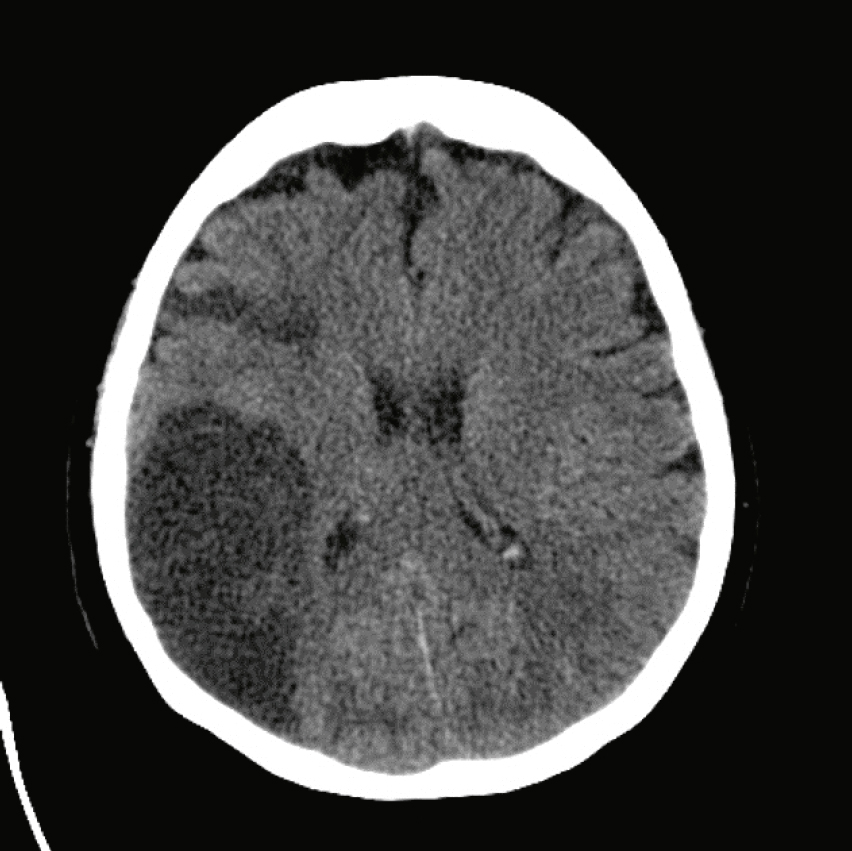

La lésion suivante chez un patient droitier (fig. 32.8) peut être associée avec un ou plusieurs des symptômes suivants : lequel ou lesquels ?

Cette coupe axiale d’un scanner cérébral sans injection met en évidence un hématome intracérébral spontané ou post-traumatique siégeant dans le lobe temporal gauche. La collection apparaît spontanément hyperdense, bien limitée, et refoule les structures adjacentes, traduisant un effet de masse modéré. L’hématome s’étend vers la région cortico-sous-corticale et comprime partiellement la corne temporale du ventricule latéral gauche. La ligne médiane est légèrement déviée vers la droite, sans signes francs d’engagement. L’aspect homogène de la densité, sans zones hypo- ou iso-denses, oriente vers un saignement récent. Les sillons corticaux environnants sont effacés, indiquant un œdème périphérique associé. Cette image évoque une hémorragie lobaire isolée, à prendre en charge rapidement pour éviter l’aggravation neurologique.